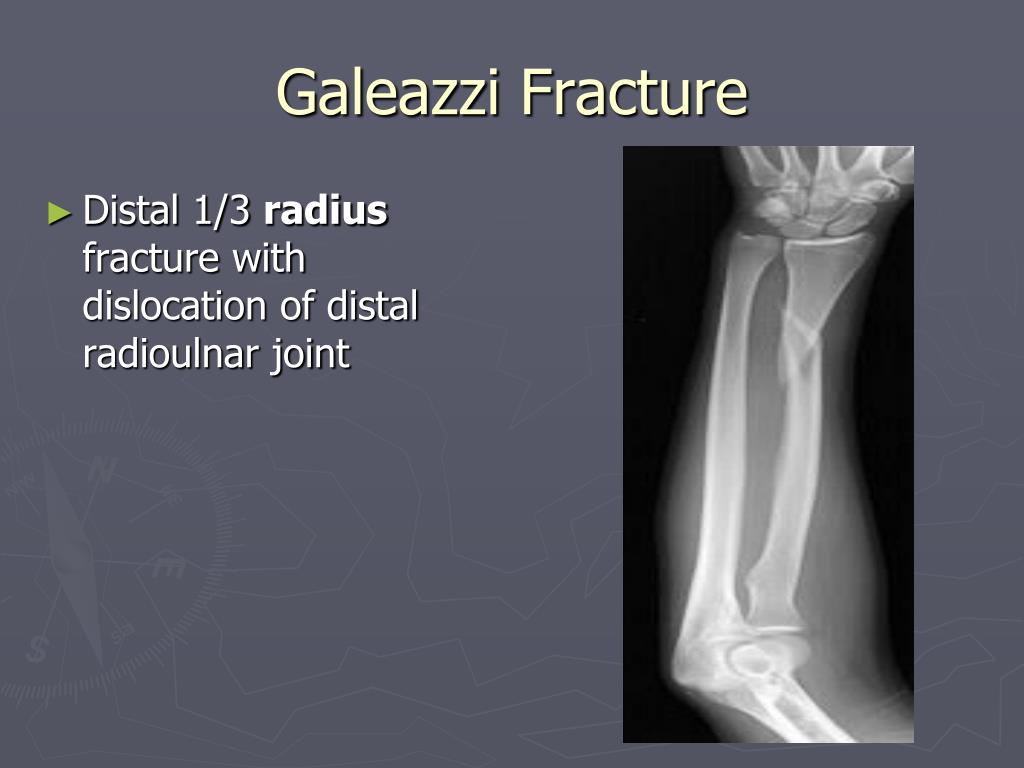

Galeazzi fracture diagram skin#